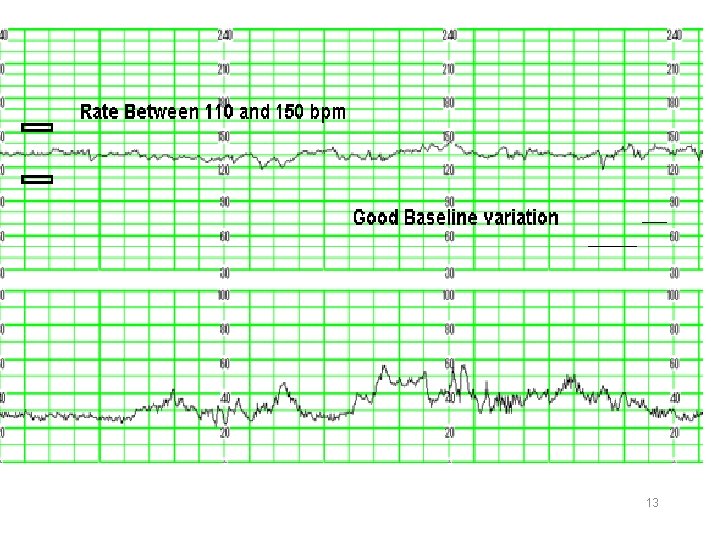

Baseline variability The minor fluctuations in baseline FHR occuring at three to five cycles per minute. It is measured by estimating the difference in beats per minute between the highest peak and lowest trough of fluctuation in a one-minute segment of the trace.

FHR Variability Absent variability = Amplitude range undetectable Minimal = < 5 BPM Moderate = 6 to 25 BPM Marked = > 25 BPM

Category I All of the following criteria must be present. Tracings meeting these criteria are predictive of normal fetal acidbase balance at the time of observation. Baseline rate: 110 to 160 bpm Moderate baseline FHR variability No late or variable decelerations Early decelerations may be present or absent Accelerations may be present or absent